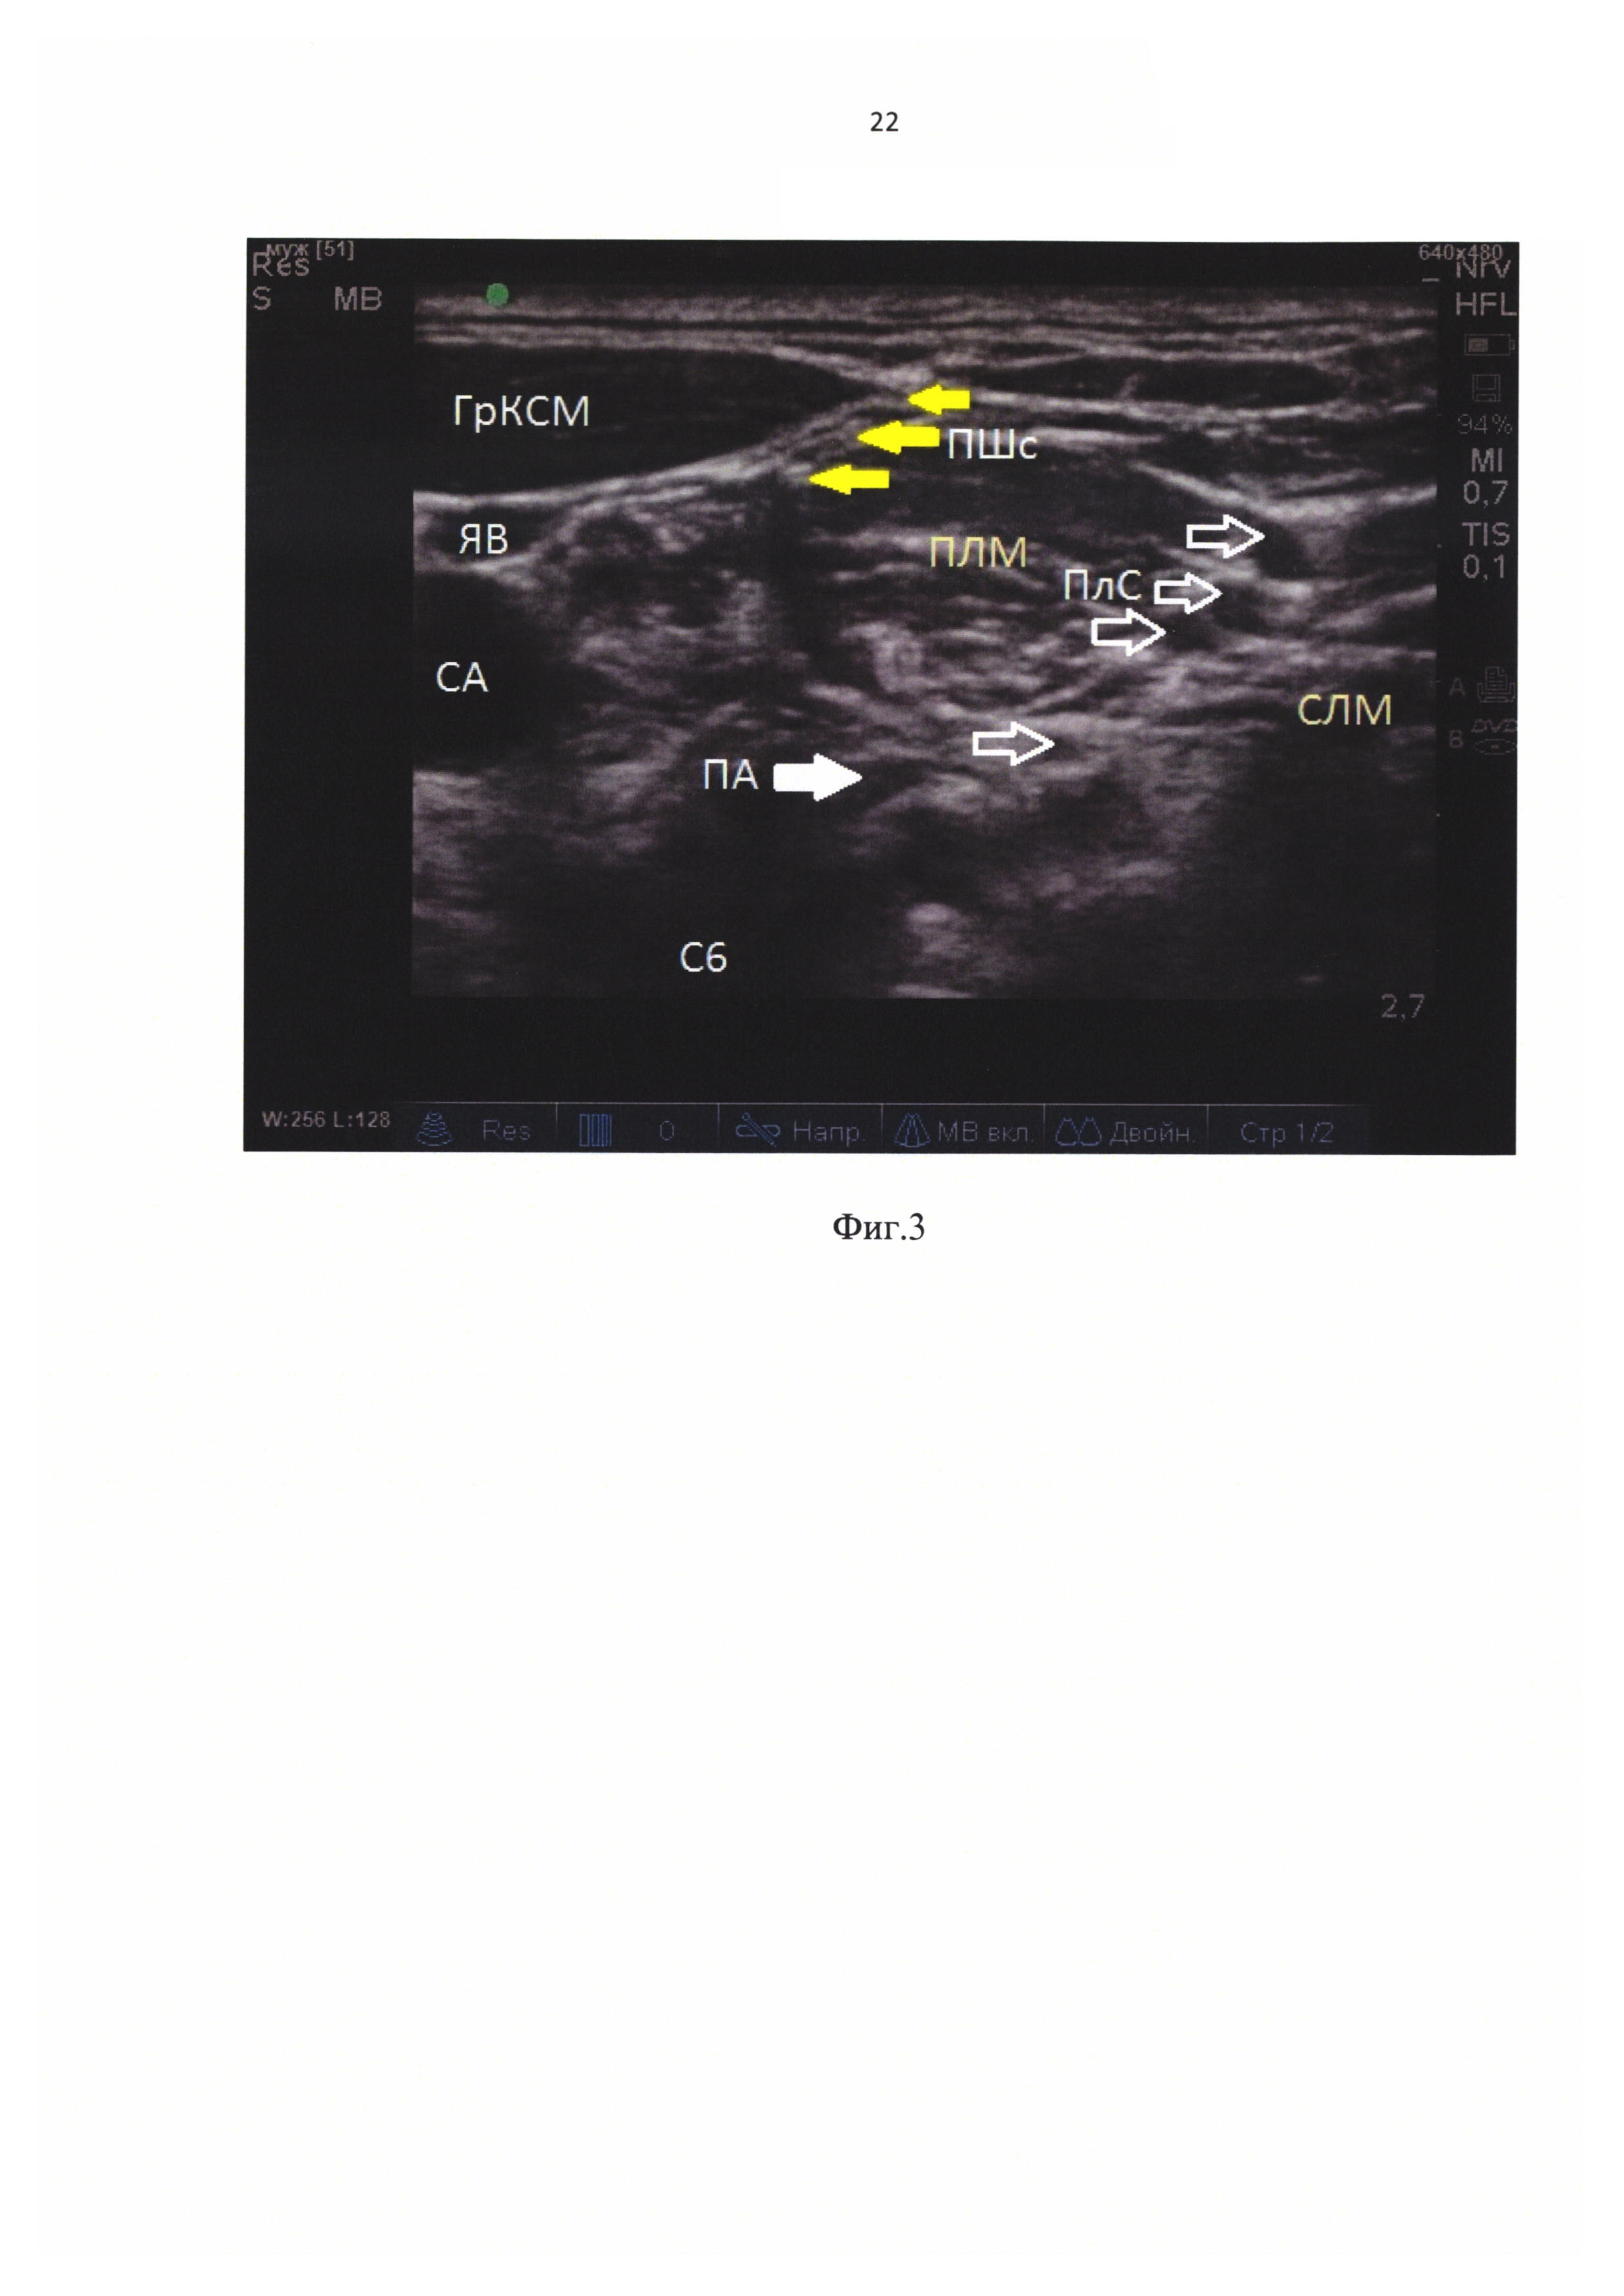

[30]

На фиг. 3 показан вариант вкола иглы латеральнее датчика. Используются следующие обозначения: 1 - плечевое сплетение, 5 - позвоночная артерия.